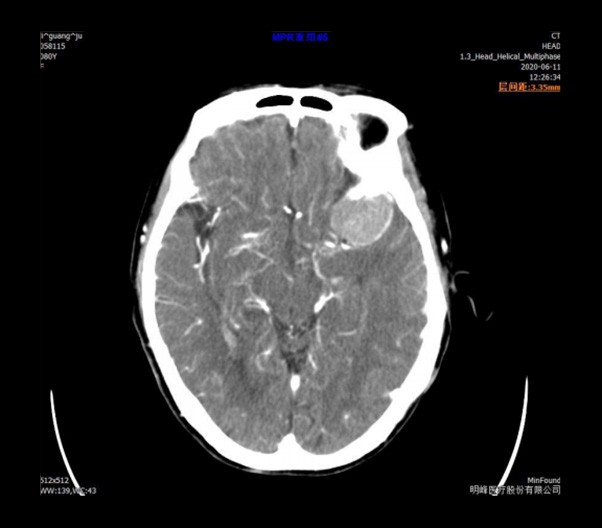

ScintCare Blue 755 | up to 64 slices

ScintCare Blue 755 incorporates an entirely digital integrated ScintiStar detector, which was solely developed by MinFound, from material to the whole structure design, based on the technical know-how of our skilled scientific team. The system produces high-resolution images with a low radiation dose and an excellent signal-to-noise ratio.

NDI NanoDose iteration algorithm is an innovative iterative technique for image reconstruction that takes full advantage of deep learning in anatomical structure in image space as well as model-driven iteration involving tube and detector in projection space, with the aim to generate sharp images in high resolution at the lowest possible dose.

臨床畫廊